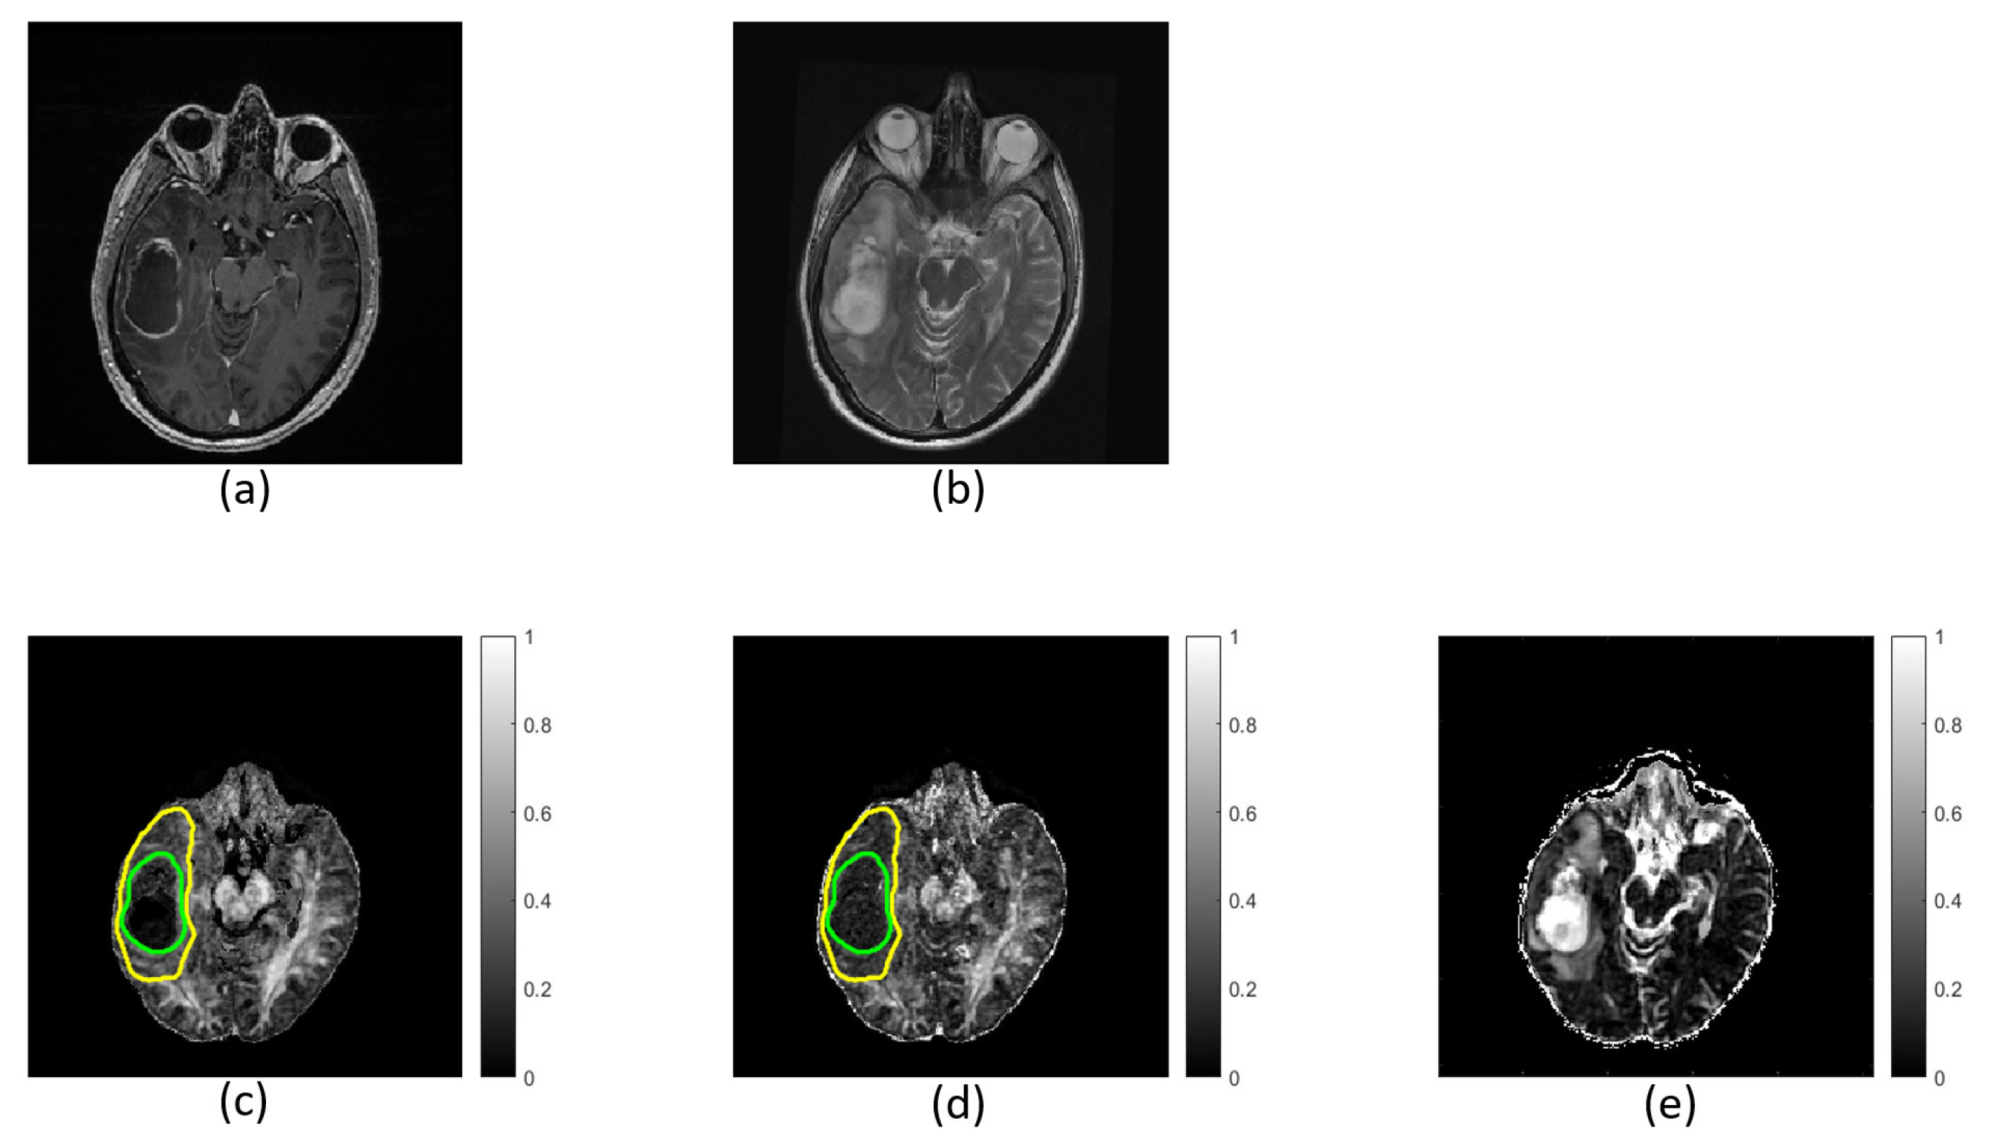

Based on the T1w- and T2w-images, a neuroradiologist with 8 years of experience manually outlined regions of interest (ROIs) encompassing the entire lesion, including the peritumoral region (total tumor volume), the enhancing lesion (enhancing tumor region), and the non-enhancing, presumed necrotic core (necrotic tumor region) (Figure 1). ROIs for the non-enhancing tissue (non-enhancing tumor region) were calculated by subtracting the enhancing tumor region and necrotic tumor region from the total tumor region. The tumor grades were confirmed by histology according to the 2016 WHO criteria [33,34].

Figure 1. Masks in a grade IV patient overlaid on structural T1w images. The yellow boundary shows the total tumor region (a); the area between the green and purple boundaries shows the enhancing tumor region (b); the area within the purple boundary shows necrotic tumor region (c); and the area between the yellow and green boundaries shows the non-enhancing tumor region (d).